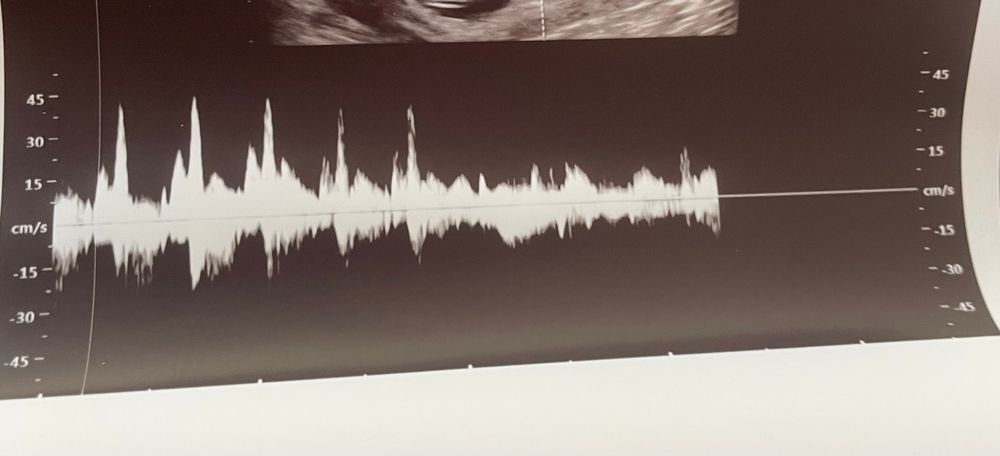

Сердцебиение плода

Скорее просто датчик слетел, доктор ж его двигает, поэтому и сбился график Если волнуетесь, сходите еще раз

Просто, вечером гляну на доплере. Всегда ритмичное. Наверное,реально датчик слетел,она недолго держала. Спасибо большое)